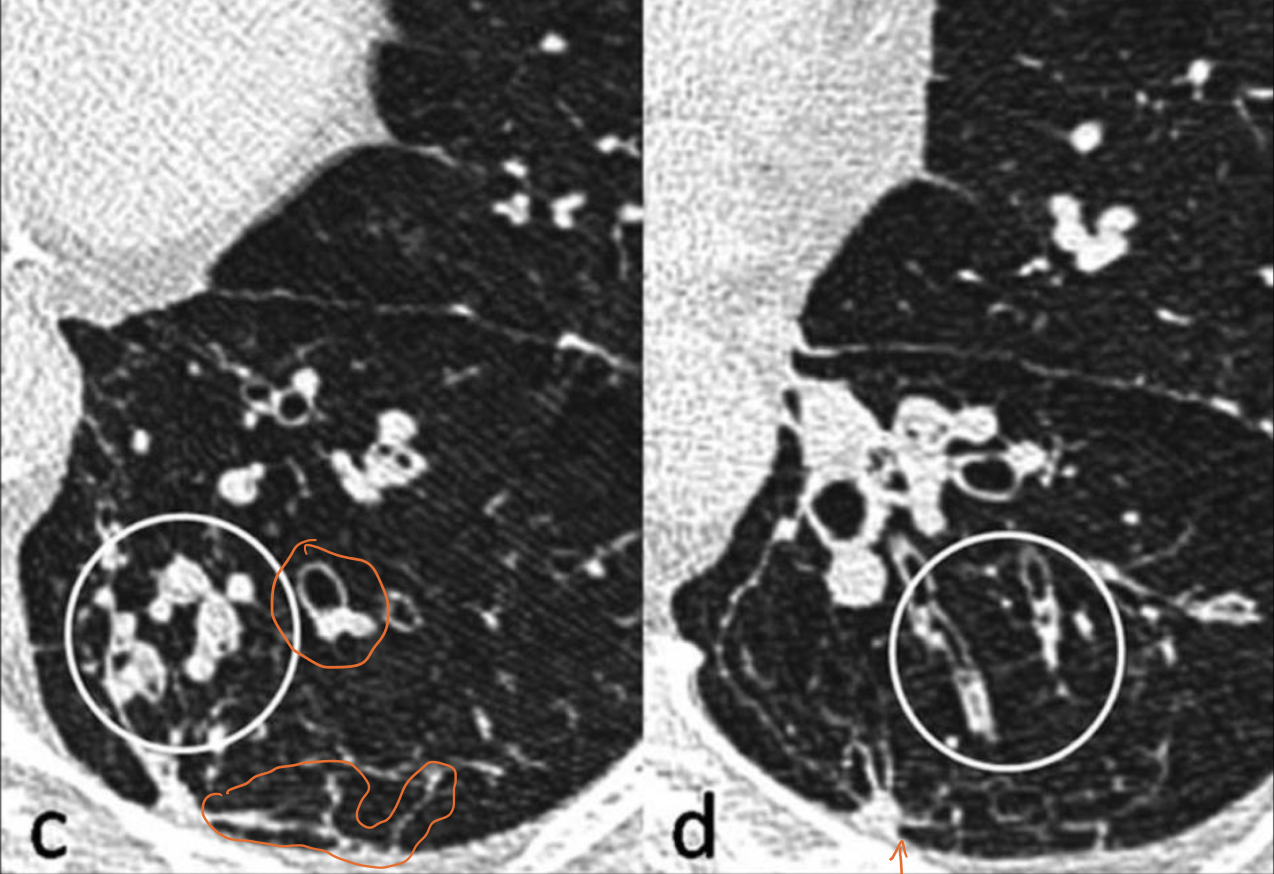

Q

Patrón que podemos ver

A

Centrolobulillar

10

Paraseptal

11

Panlobulillar